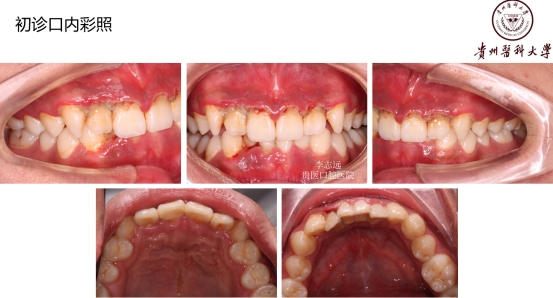

18岁,男性,经常抽烟,熬夜打游戏!!!

好发人群以及典型症状:该病好发于青壮年,多见于男性吸烟者、经常熬夜者、精神压力大者。得了这个病的话,前面描述的症状都可能会发生!牙龈的边缘及牙龈乳头发生坏死,常有黄白色假膜覆盖,很痛,有腐败臭味!!但是有这些症状时还是要小心另外一些很严重的疾病哦,比如白血病、艾滋等,得排除了它们,才能放心点。

治疗以及预后:排除了白血病、艾滋等严重疾病,明确诊断后,病人也不要过分担心。这种病发病急,治疗效果及预后也好。治疗时去除牙石及坏死组织,局部止血,双氧水充分冲洗,口服抗厌氧菌药物替硝唑等,全身支持治疗:高蛋白饮食、维生素C等。一定要改变生活习惯,避免熬夜,戒烟,放松心情,保持口腔卫生!